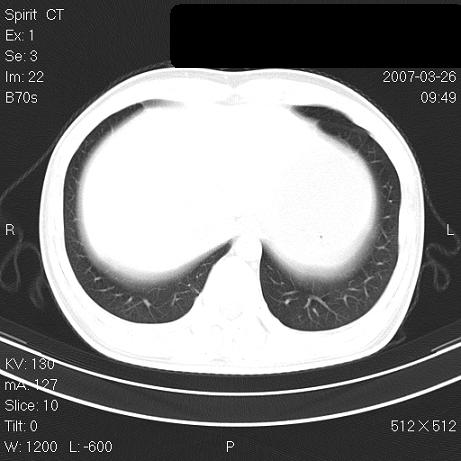

标题: CT7171B:补充治疗后2周复查 [打印本页]

标题: CT7171B:补充治疗后2周复查

治疗后2周复查,请讨论

结合以前的ct片,还是考虑肺挫伤,吸收多了。

支持:创伤性湿肺。现肺挫裂伤(出血 积气)大部分吸收。建议继续治疗!

结合以前的ct片,支持创伤性湿肺。现大部分吸收。

支持:创伤性湿肺、肺挫裂伤。现肺挫裂伤(出血、渗出、液气腔)大部分吸收。建议继续治疗!

支持:创伤性湿肺、肺挫裂伤。现肺挫裂伤(出血、渗出、液气腔)大部分吸收.

结合老片支持创伤性湿肺、肺挫裂伤。

经治疗后病灶明显吸收,考虑创伤性湿肺、肺挫裂伤